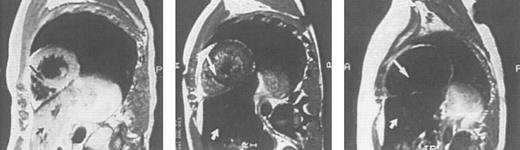

Imaging of tissue iron.Computed tomography,170-174 nuclear resonance scattering (NRS) from manganese-56,175 and the most widely used modality, magnetic resonance imaging,176-193 have all been used to evaluate tissue iron stores in vitro and in vivo, but none is clinically available for the measurement of hepatic iron concentrations. Biopsy-demonstrated reductions in hepatic iron have been reflected by magnetic resonance imaging (MRI) in individual patients192 (Fig 3), but correlations between hepatic iron concentrations determined by biopsy and those estimated by magnetic resonance have varied with differences in both equipment and method. Magnetic resonance represents the only imaging method in clinical use with the potential to detect iron within the heart189,192,193 (Fig 4). Although imprecision in the quantitation of cardiac iron obtained at biopsy194,195 prevents direct correlation with values of cardiac iron estimated by MRI in humans, good correlation between MRI-derived, and biopsy-determined, cardiac iron has been observed in a thalassemic mouse model.193 Furthermore, MRI changes consistent with the reduction of cardiac iron (Fig 5) that are paralleled by improvement in cardiac function have been reported in individual patients.192 Similarly, MRI studies of the iron-loaded anterior pituitary gland196,197 have reported variations in pituitary iron that are correlated with pituitary reserve in individual patients with thalassemia.198 In summary, although many studies show that MRI can reflect the presence of, and changes in, tissue iron in vivo, this method has not been validated as one that provides measurements of tissue iron that are quantitatively equivalent to those determined at tissue biopsy.

Sagittal MRI of the heart in three patients with homozygous β thalassemia and transfusional iron overload. (A, left) Normal signal from the septum (long arrow) and posterior wall of the heart, consistent with the presence of very mild cardiac iron loading, in a transfused patient regularly complianct with iron chelating therapy. The homogenous signal of the liver, consistent with very mild iron loading in this organ (short arrow), is also seen below the image of the heart. (B, middle): Imhomogenity of signal from the septum (long arrow) and posterior wall, consistent with moderate iron deposition in a transfused patient erratically compliant with iron chelating therapy. Loss of liver signal (short arrow) is consistent with heavier iron loading in this organ. (C, right): Absence of signal from the septum (arrow), posterior wall and liver (short arrow), compatible with heavy iron deposition in a transfused patient who has been noncompliant with iron chelating therapy over several years.